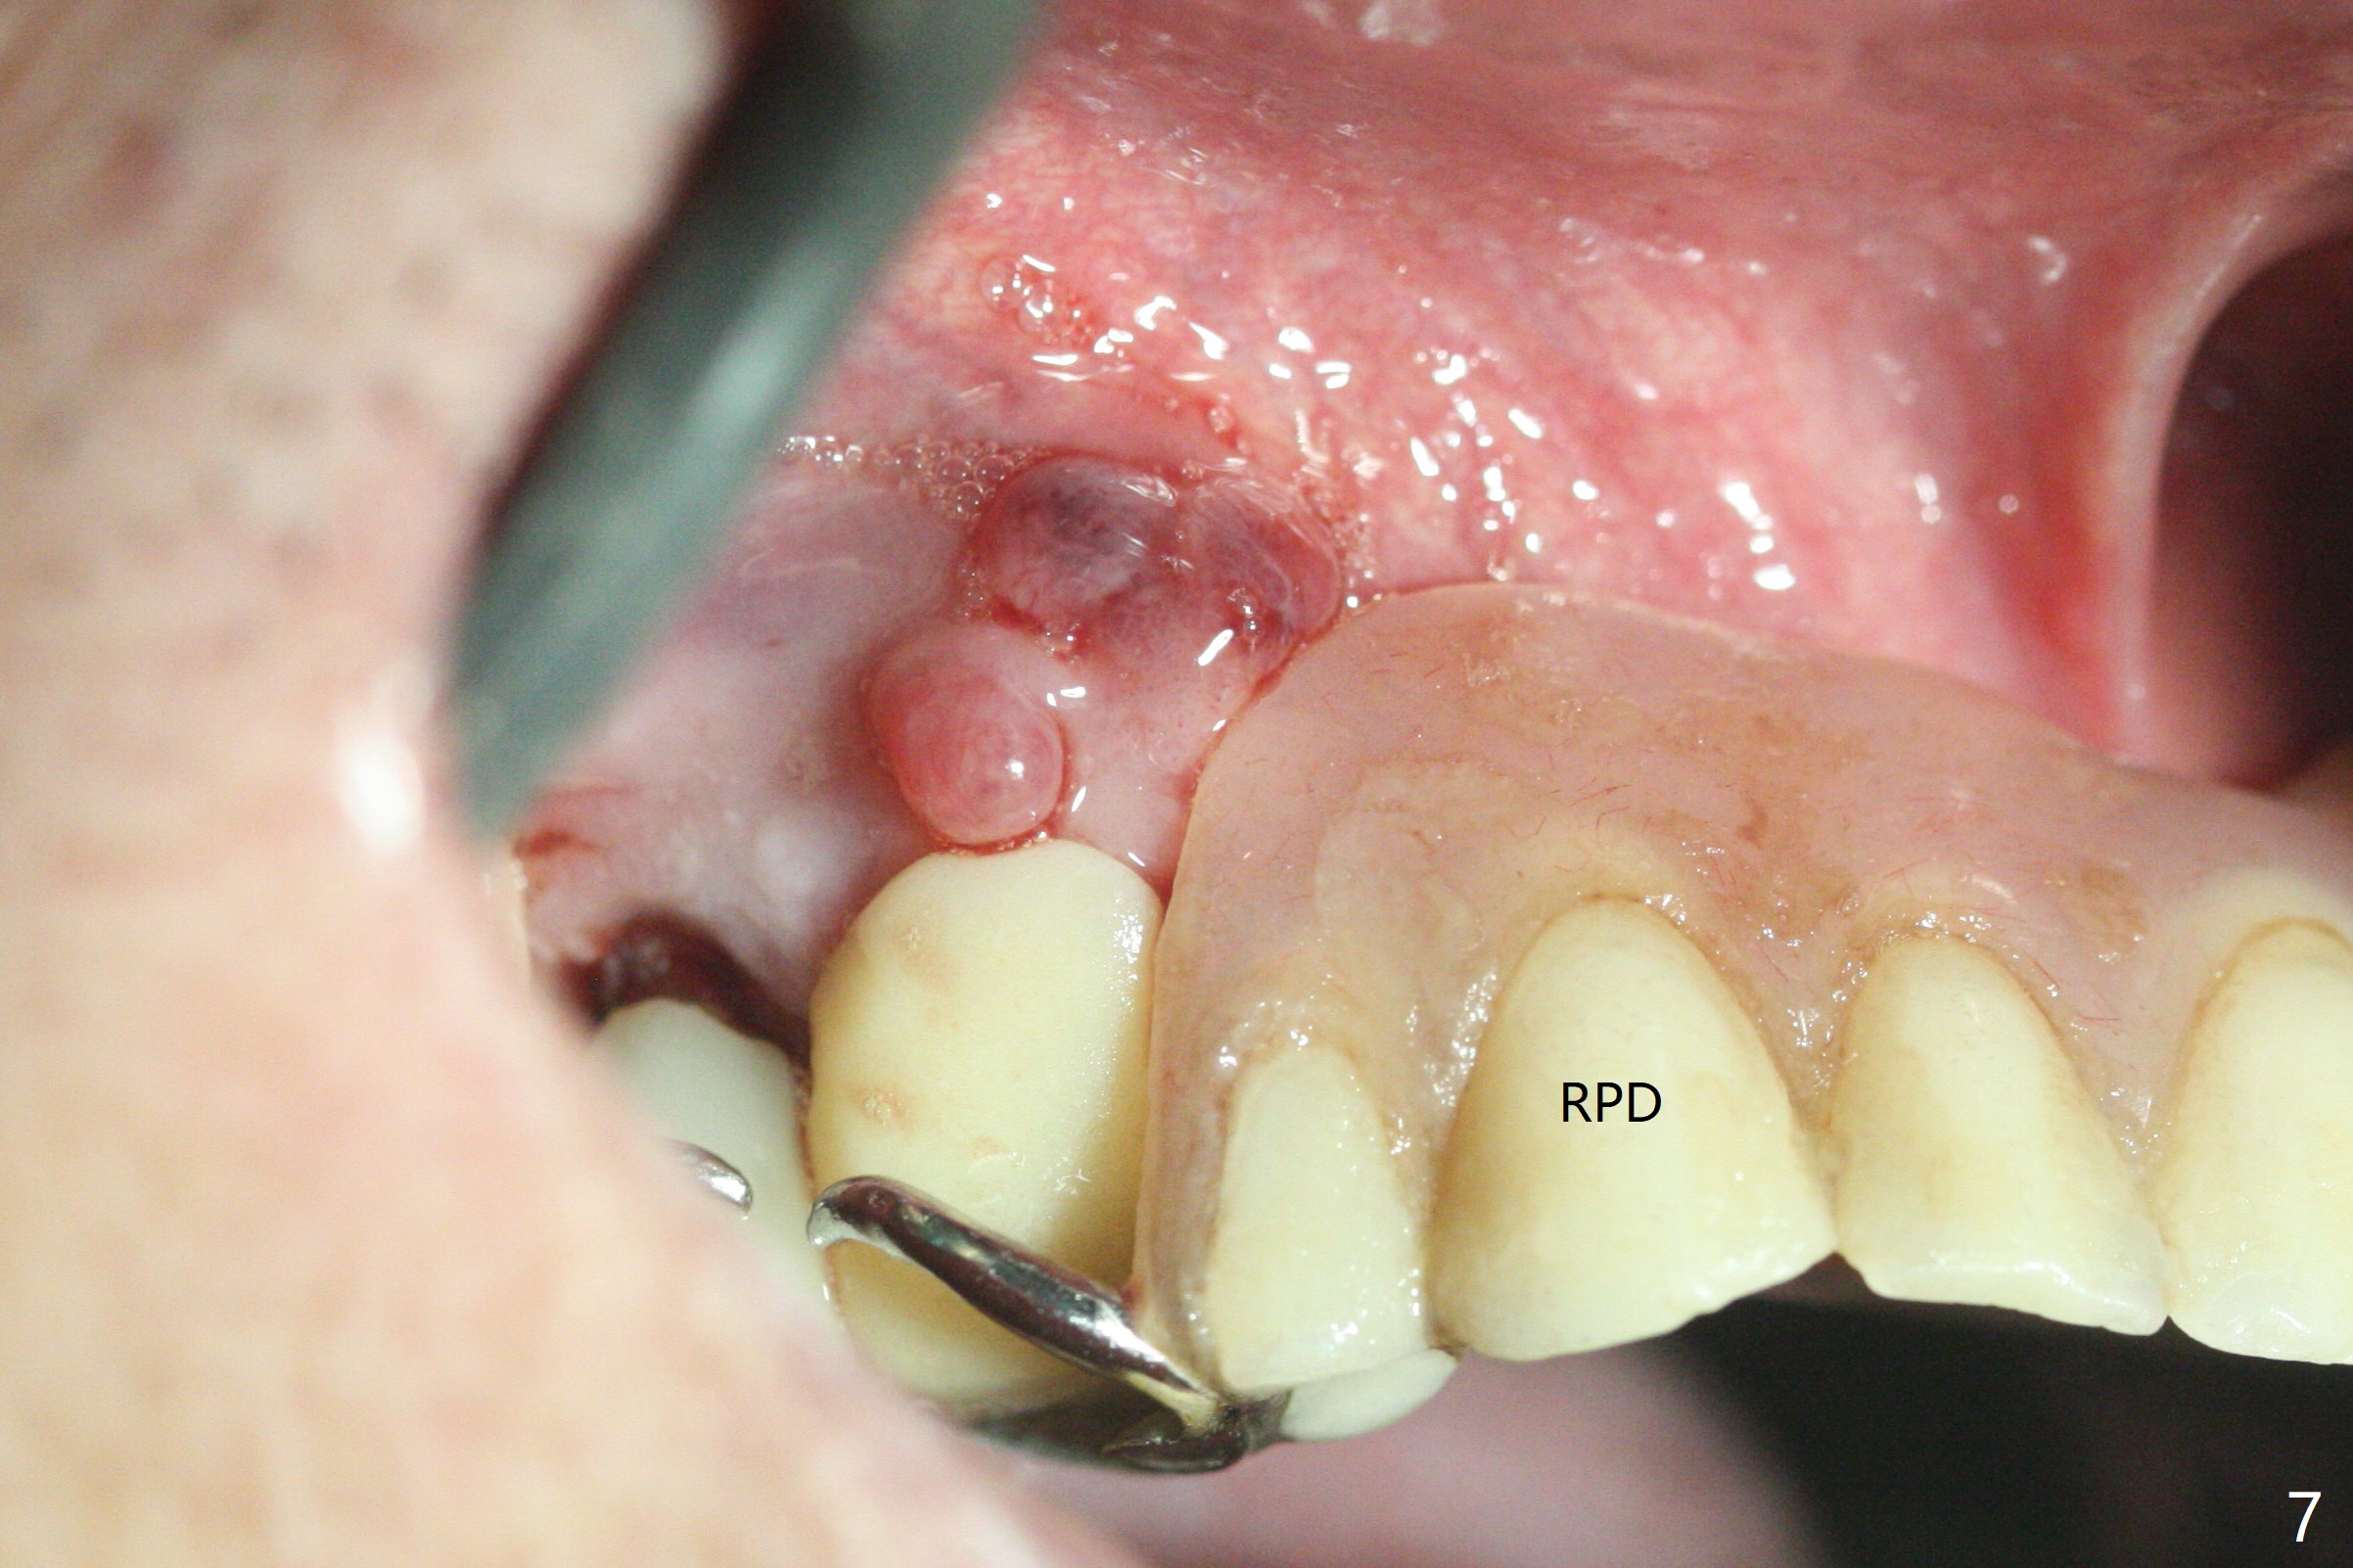

部分断裂的5号牙颊侧根尖有3个瘘道(图一),五类(颈部)缺损,严重牙龈退缩。牙齿拔除过程中断裂,需要手机切断拔除,颊侧骨板缺失,钻洞起源于牙槽窝腭侧(融合根,图二,五),植入4x13毫米长植体,根尖骨大约4毫米,植体也卡入近中,远中骨壁,扭力大于35Ncm,即刻放置基台,颊侧间隙(图三至五:*)放入粘性骨粉,牙槽窝口用PRF穿过基台关闭(图五),接着制作临时牙冠(图六:T),多次衬里严密关闭牙槽窝,而咬合面低,最后插入活动托牙(图七:RPD,左侧有两个基牙)。Return to Protect Graft Torque Xin Wei, DDS, PhD, MS 1st edition 05/18/2021, last revision 05/18/2021